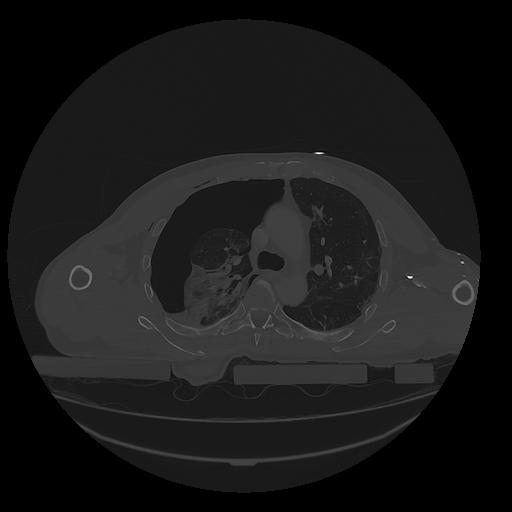

31 PULMON,CE,Vol,1.0,PULMON,,